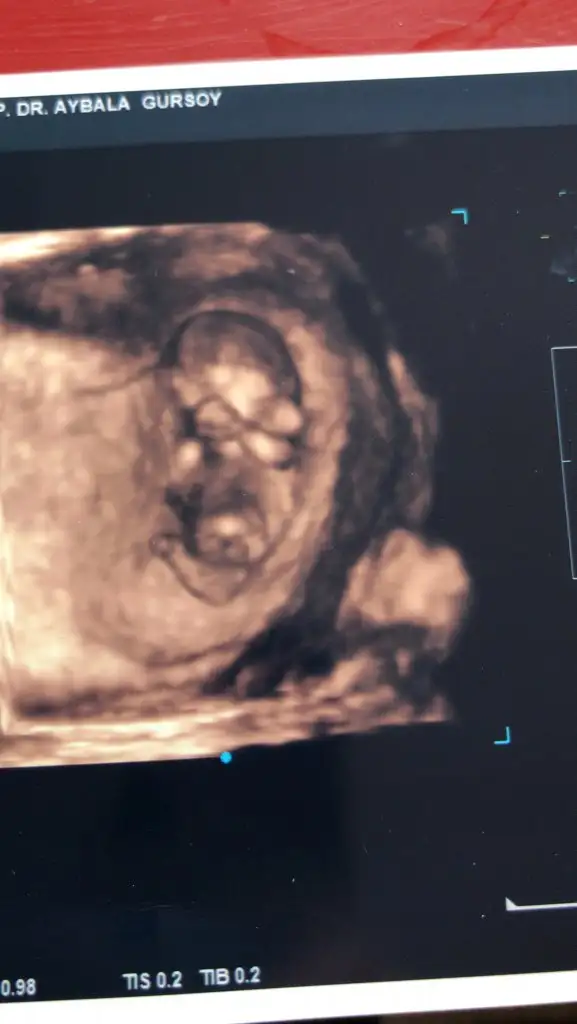

Bende kesin birşey demiyorum canım emin olamadım hayırlısı olsunValla canım ben hiç anlamıyorum nubtan falan sen maşallah çizmişsin bir deyan profilden göstertiginde biberon ucu gibi sivri dik bisey gösterdi biz bu dikligi görünce erkek diye yorumlarız dedi sonra bacak arasını da açıp gösterince evet burda da erkek görünüyor dedi ama yinede bir dahaki kontrolde daha netleşir dedi. Hatta ben kız hissediyorum babamız erkek hissediyor dedim baba haklı çıkacak sanırım dedi. Hayırlısı bakalım sağlıklı sıhhatli olsunda ❤

doktor tahmin de bulunmadı mı canım kız gibi geldi banaEki Görüntüle 2707453

17 haftalıktekrar atarsınız demiştiniz bu sefer sanki daha belirgin tahmininizi alabilirmiyim ❣ Ikra meyra

Bu sefer doktorumuz tahminde bulundu ama ben meyra hanıma da sormak istedimdoktor tahmin de bulunmadı mı canım kız gibi geldi bana

Erkek görünüyor

Evet yaa biraz üstte oluyor demekki 17+ da pipi olusunca az önce bu gördüğüm pipi ise tabikiTeşekkür ederim benimde gönlüm kız hep öyle hissetim ama erkek dedi doktorum bugün değişirmi bilmiyorumçok teşekkür ederim cevabınız için

Aaa siz işaretleyince gördüm bugün bana 4 kere gösterdi görmüyormusun şekerim pipi bu pipi kız yok dedi doktorEvet yaa biraz üstte oluyor demekki 17+ da pipi olusunca az önce bu gördüğüm pipi ise tabiki